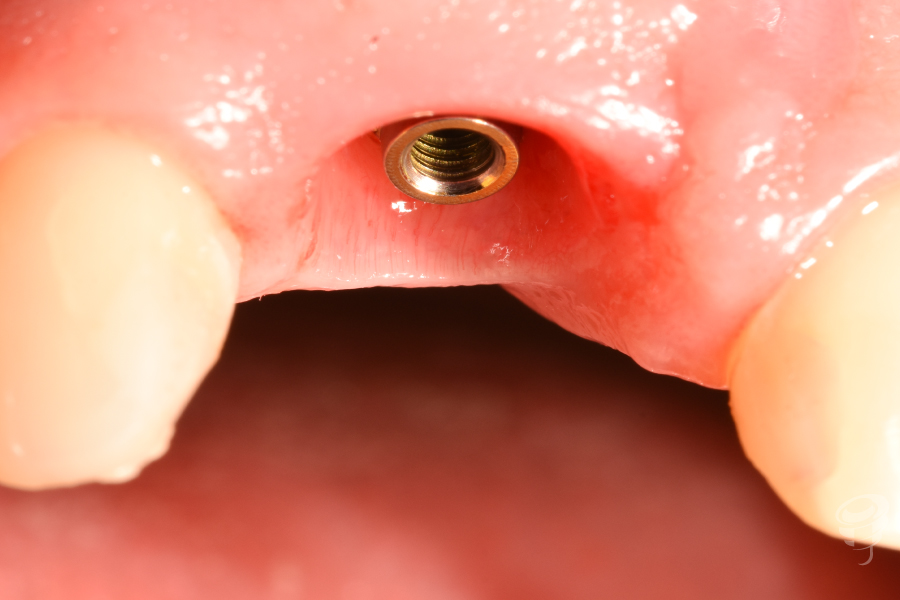

- Colocación del implante: Implante cónico de titanio grado IV (IPX 4012) con torque de inserción de 40 Ncm. Posición: 3mm apical al CEN del diente adyacente, 2mm palatino a la tabla vestibular.

Figura 9

Figura 10